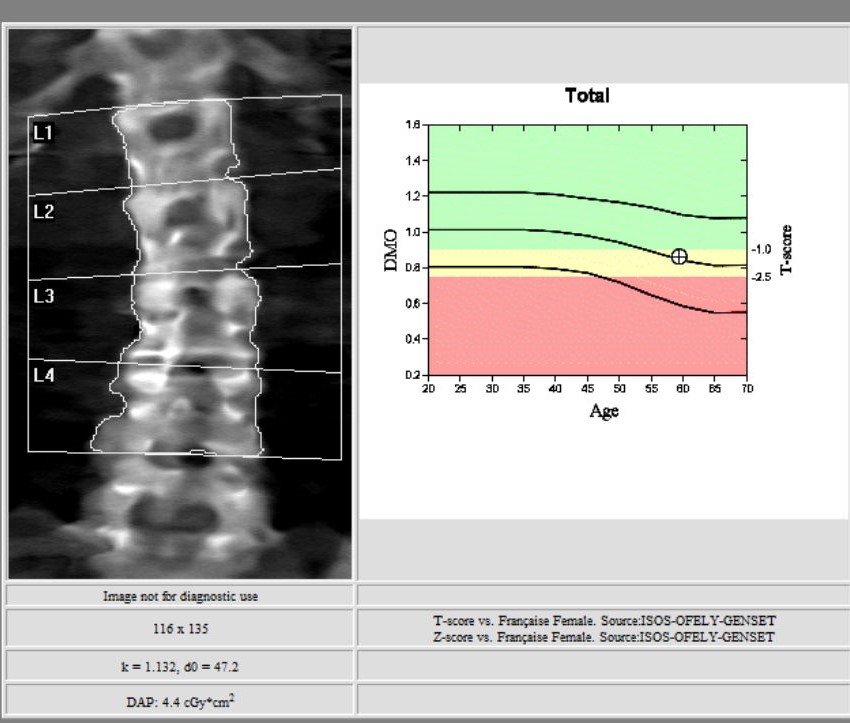

L’ostéodensitométrie mesure précisément la densité osseuse au niveau de deux sites principaux (souvent le rachis lombaire et le col fémoral), grâce à une technique dite biphotonique utilisant deux faisceaux de rayons X à très faible dose.

Elle constitue aujourd’hui la méthode la plus précise et la plus fiable pour diagnostiquer l’ostéoporose et évaluer le risque de fracture.

Les deux zones habituelles analysées sont :

1. le rachis lombaire ;

Elles permettent une estimation fiable du risque fracturaire.